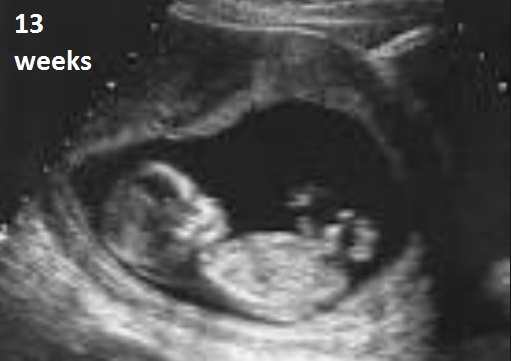

I had to have seven amnios with my youngest child. They were all ultrasound guided, plus I could feel her inside, and it was clear from the very first procedure that she did not like that needle coming into her personal space one little bit.

The amnios were about 2 weeks apart. Each time I went for an appointment, my unborn daughter would become agitated earlier and earlier in the appointment. Outside odors get into the amniotic fluid where the baby can taste and smell them and the smells in that office were unlike anything I normally experienced.

It was clear to me that she hated the needle and that she learned what smells, and maybe sounds, meant it would be coming in soon. By the last amnio, my daughter was kicking and rolling before they even started prepping me.

She was so agitated, the doctor had a hard time safely getting samples during the last few procedures. Finally, they resorted to shoving on the top of her head to make her curl up tighter in my womb, then while the nurse held her there, the doctor stuck the needle into the small space below the nurse’s hand to get the sample he needed.